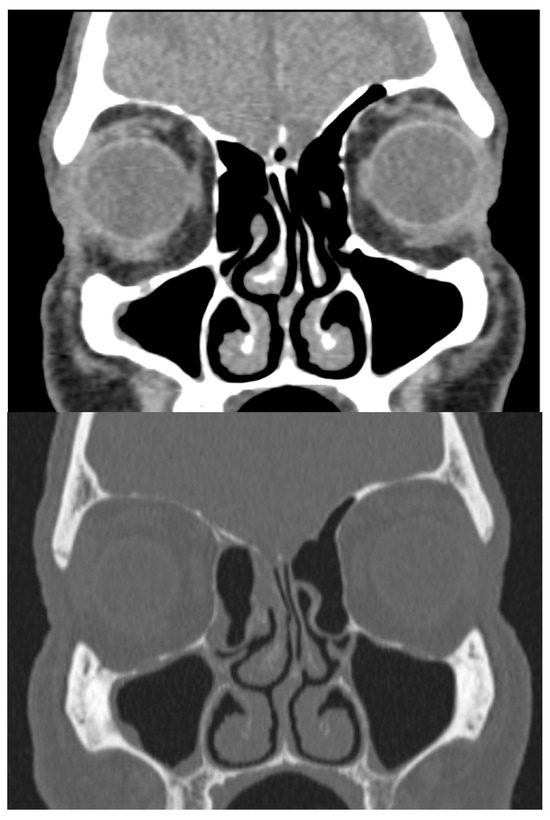

Physical examination revealed a large mass occupying the entire lumen of the right nasal cavity. There was no initial evidence of septal perforation. A computed tomography (CT) scan of the paranasal sinuses showed left septal deviation but failed to explain the origin of the mucosal mass (Figure 1). Due to persistent symptoms and obstructive findings, a septoplasty was performed.

Figure 1. CT scan in bone and soft-tissue windows showing septal deviation. Anterior curving is shown towards the left nasal fossa with a right inferior spur in contact with the ipsilateral middle turbinate and hypertrophy of the inferior turbinates.